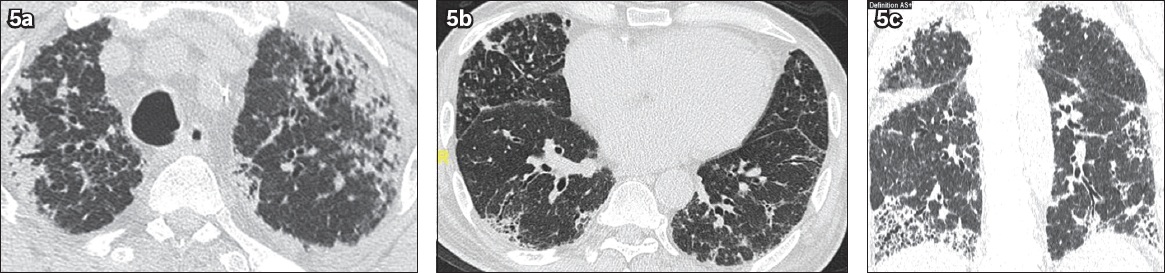

Fig. 5

CT images of a 71-year-old man with pleuroparenchymal fibroelastosis show (a) bilateral subpleural fibrotic changes with traction bronchiectasis in the upper lobes; (b) ‘free-standing’ bronchiectasis, which may reflect recurrent aspiration, in the middle lobe; and (c) a typical interstitial pneumonia pattern with subpleural reticulation, traction bronchiectasis and honeycombing in the lung bases.